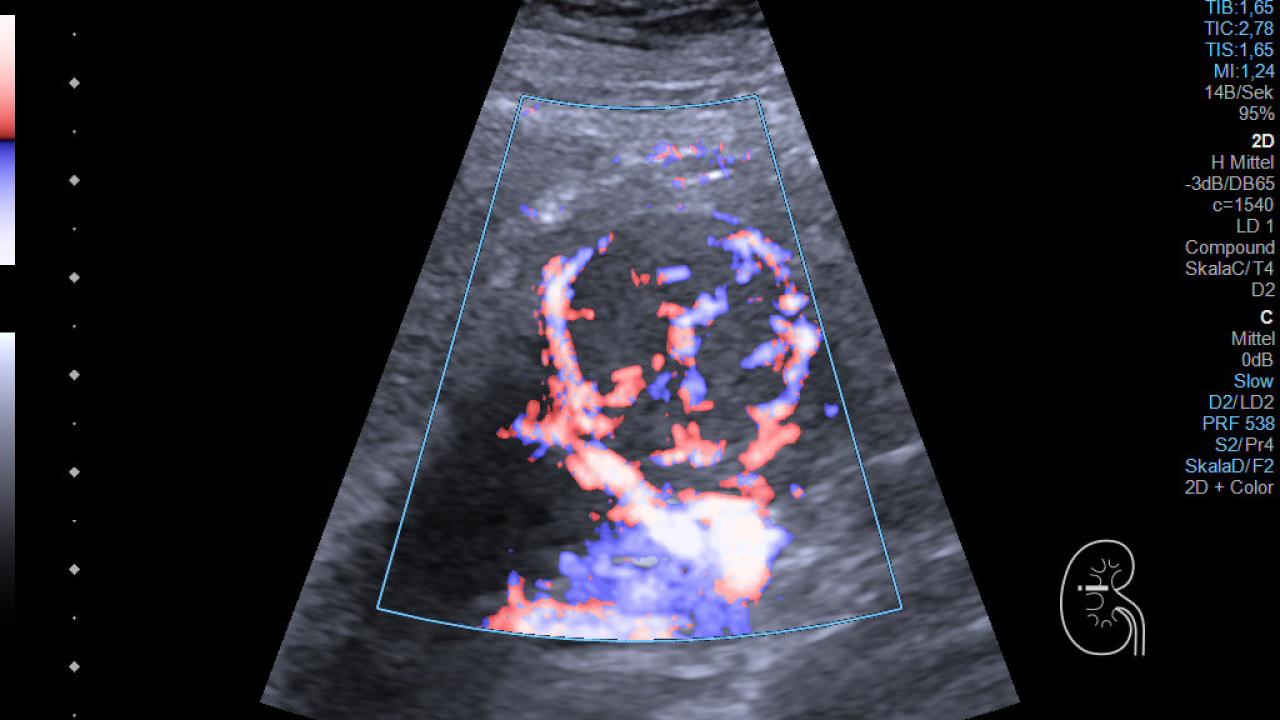

Die optimale Diagnostik und Therapie von Nierentumoren erfordern ein individualisiertes und interdisziplinäres Vorgehen. Daher hat sich die Klinik für Urologie gemeinsam mit dem internistischen Ultraschall-Labor der Abteilung für Nephrologie und dem Institut für Radiologie zum interdisziplinären Nierentumorboard zusammengeschlossen.

Hier wird für jede Patientin und jeden Patienten individuell die Diagnose und beste Behandlungsstrategie in einem interdisziplinären Nephrologisch-urologisch-radiologischen Konsens festgelegt, wobei die Befunde in der Konferenz aufwendig mit CT/MRT und mit Ultraschall in Parallelprojektion unter Berücksichtigung von Klinik und Komorbiditäten diskutiert werden.

So können wir für jeden Fall das bestmögliche Vorgehen festlegen. Ein besonderer Schwerpunkt ist das Auftreten von Nierentumoren in Transplantatnieren, die ein besonders gut abgestimmtes Vorgehen in Zusammenarbeit mit der Transplantationschirurgie erforderlich machen.